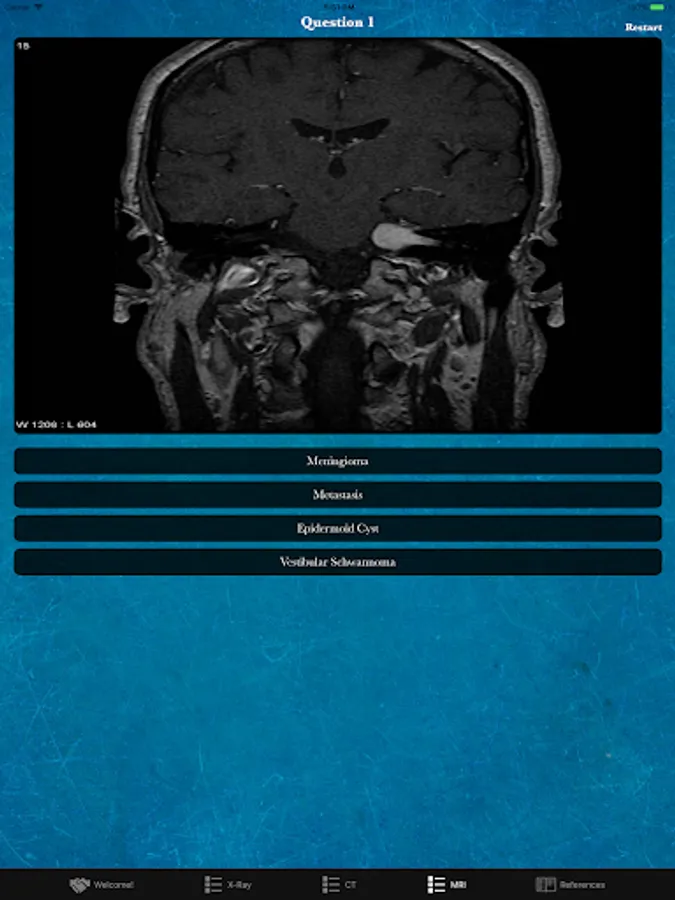

Rad Quiz is a free app developed as an introductory educational tool to expand your knowledge of medical imaging! Take our 20 question quizzes and evaluate your areas of strength and weakness. The quizzes test out three imaging modalities including X-ray, CT, and MRI. To learn more use our References tab to read up on the questions you missed. The content spans multiple specialities to give you a variety of content!